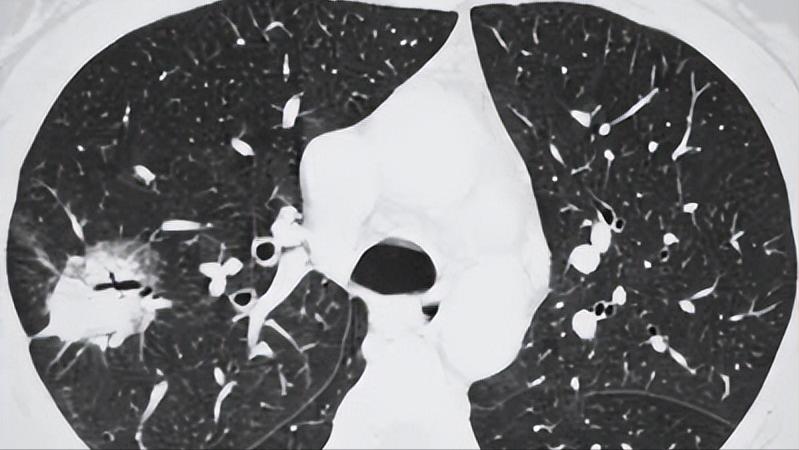

一般情况下,我们把影像学表现为直径小于或等于30毫米的肺部阴影称为肺结节,并且肺部阴影多体现为实性或亚实性,但是不伴有肺不张或淋巴结肿大的症状,也没有胸腔积液。

一般情况下,结节可以被分为三大类,分别是磨玻璃结节、混合结节和实性结节,不同的结节情况不同,就拿实性结节为例,如果结节的表面较为圆小光滑,那么很有可能就是良性。

但是一定要注意,如果为部分实性结节,那么最终恶变的概率就比较高。因为此类结节被定义为高危结节,如果患有这种结节,应该由胸外科、肿瘤外科、呼吸科和影像科的医生集体会诊,决定是否需要进行更详细的检查。